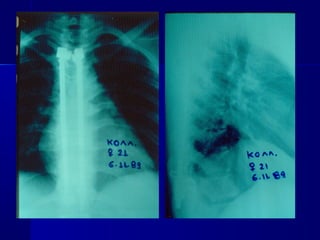

FFRRAACCTTUURREESS--

DDIISSLLOOCCAATTIIOONNSS

OOFF TTHHEE

LLOOWWEERR CCEERRVVIICCAALL

SSPPIINNEE

 Compression fractures aarree cchhaarraacctteerriizzeedd bbyy

ffaaiilluurree ooff tthhee aanntteerriioorr ccoolluummnn uunnddeerr

ccoommpprreessssiioonn wwiitthh iinnttaacctt mmiiddddllee aanndd ppoosstteerriioorr

ccoolluummnnss:: tthheessee aarree ssttaabbllee iinnjjuurriieess

 WWhheenn tthhee aanntteerriioorr aanndd mmiiddddllee ccoolluummnnss ffaallll

uunnddeerr aaxxiiaall llooaaddiinngg ffoorrcceess,, aa bbuurrsstt ffrraaccttuurree iiss

pprroodduucceedd